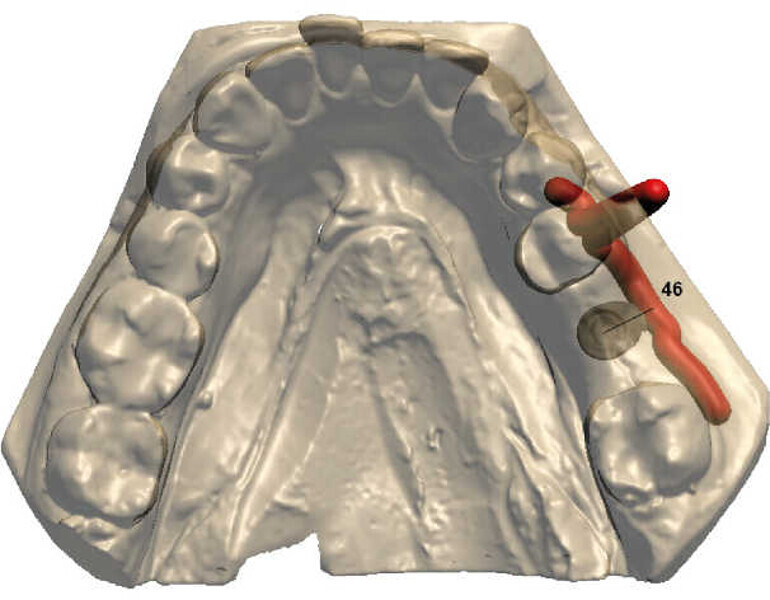

Planification implantaire numérique La marque, la taille et le diamètre des implants ont été choisis en amont sur indication du praticien, et peuvent être également géré par le laboratoire. Les implants sont positionnés selon l’axe prothétique idéal, tout en respectant la quantité d’os résiduel et les règles de sécurité (distance entre l’implant et les dents adjacentes, etc.).

Le bon positionnement de l’implant ainsi que son émergence au niveau de la future prothèse sont vérifiés (Figs. 4 et 5).

Fig. 4 : Planification implantaire.

Fig. 5 : Rapport chirurgical.